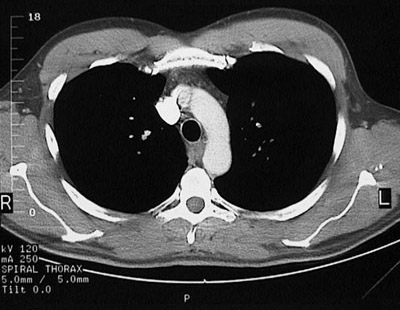

[T5] This is a normal chest CT scan demonstrating the right lung and left lung and pectoralis major muscle and pectoralis minor muscle and superior vena cava and aortic arch and manubrium of sternum and thymus and esophagus and trachea and subscapularis muscle and spine of scapula and infraspinatus muscle and trapezius muscle and rhomboid major & minor muscle and transversospinal muscle in the upper chest.